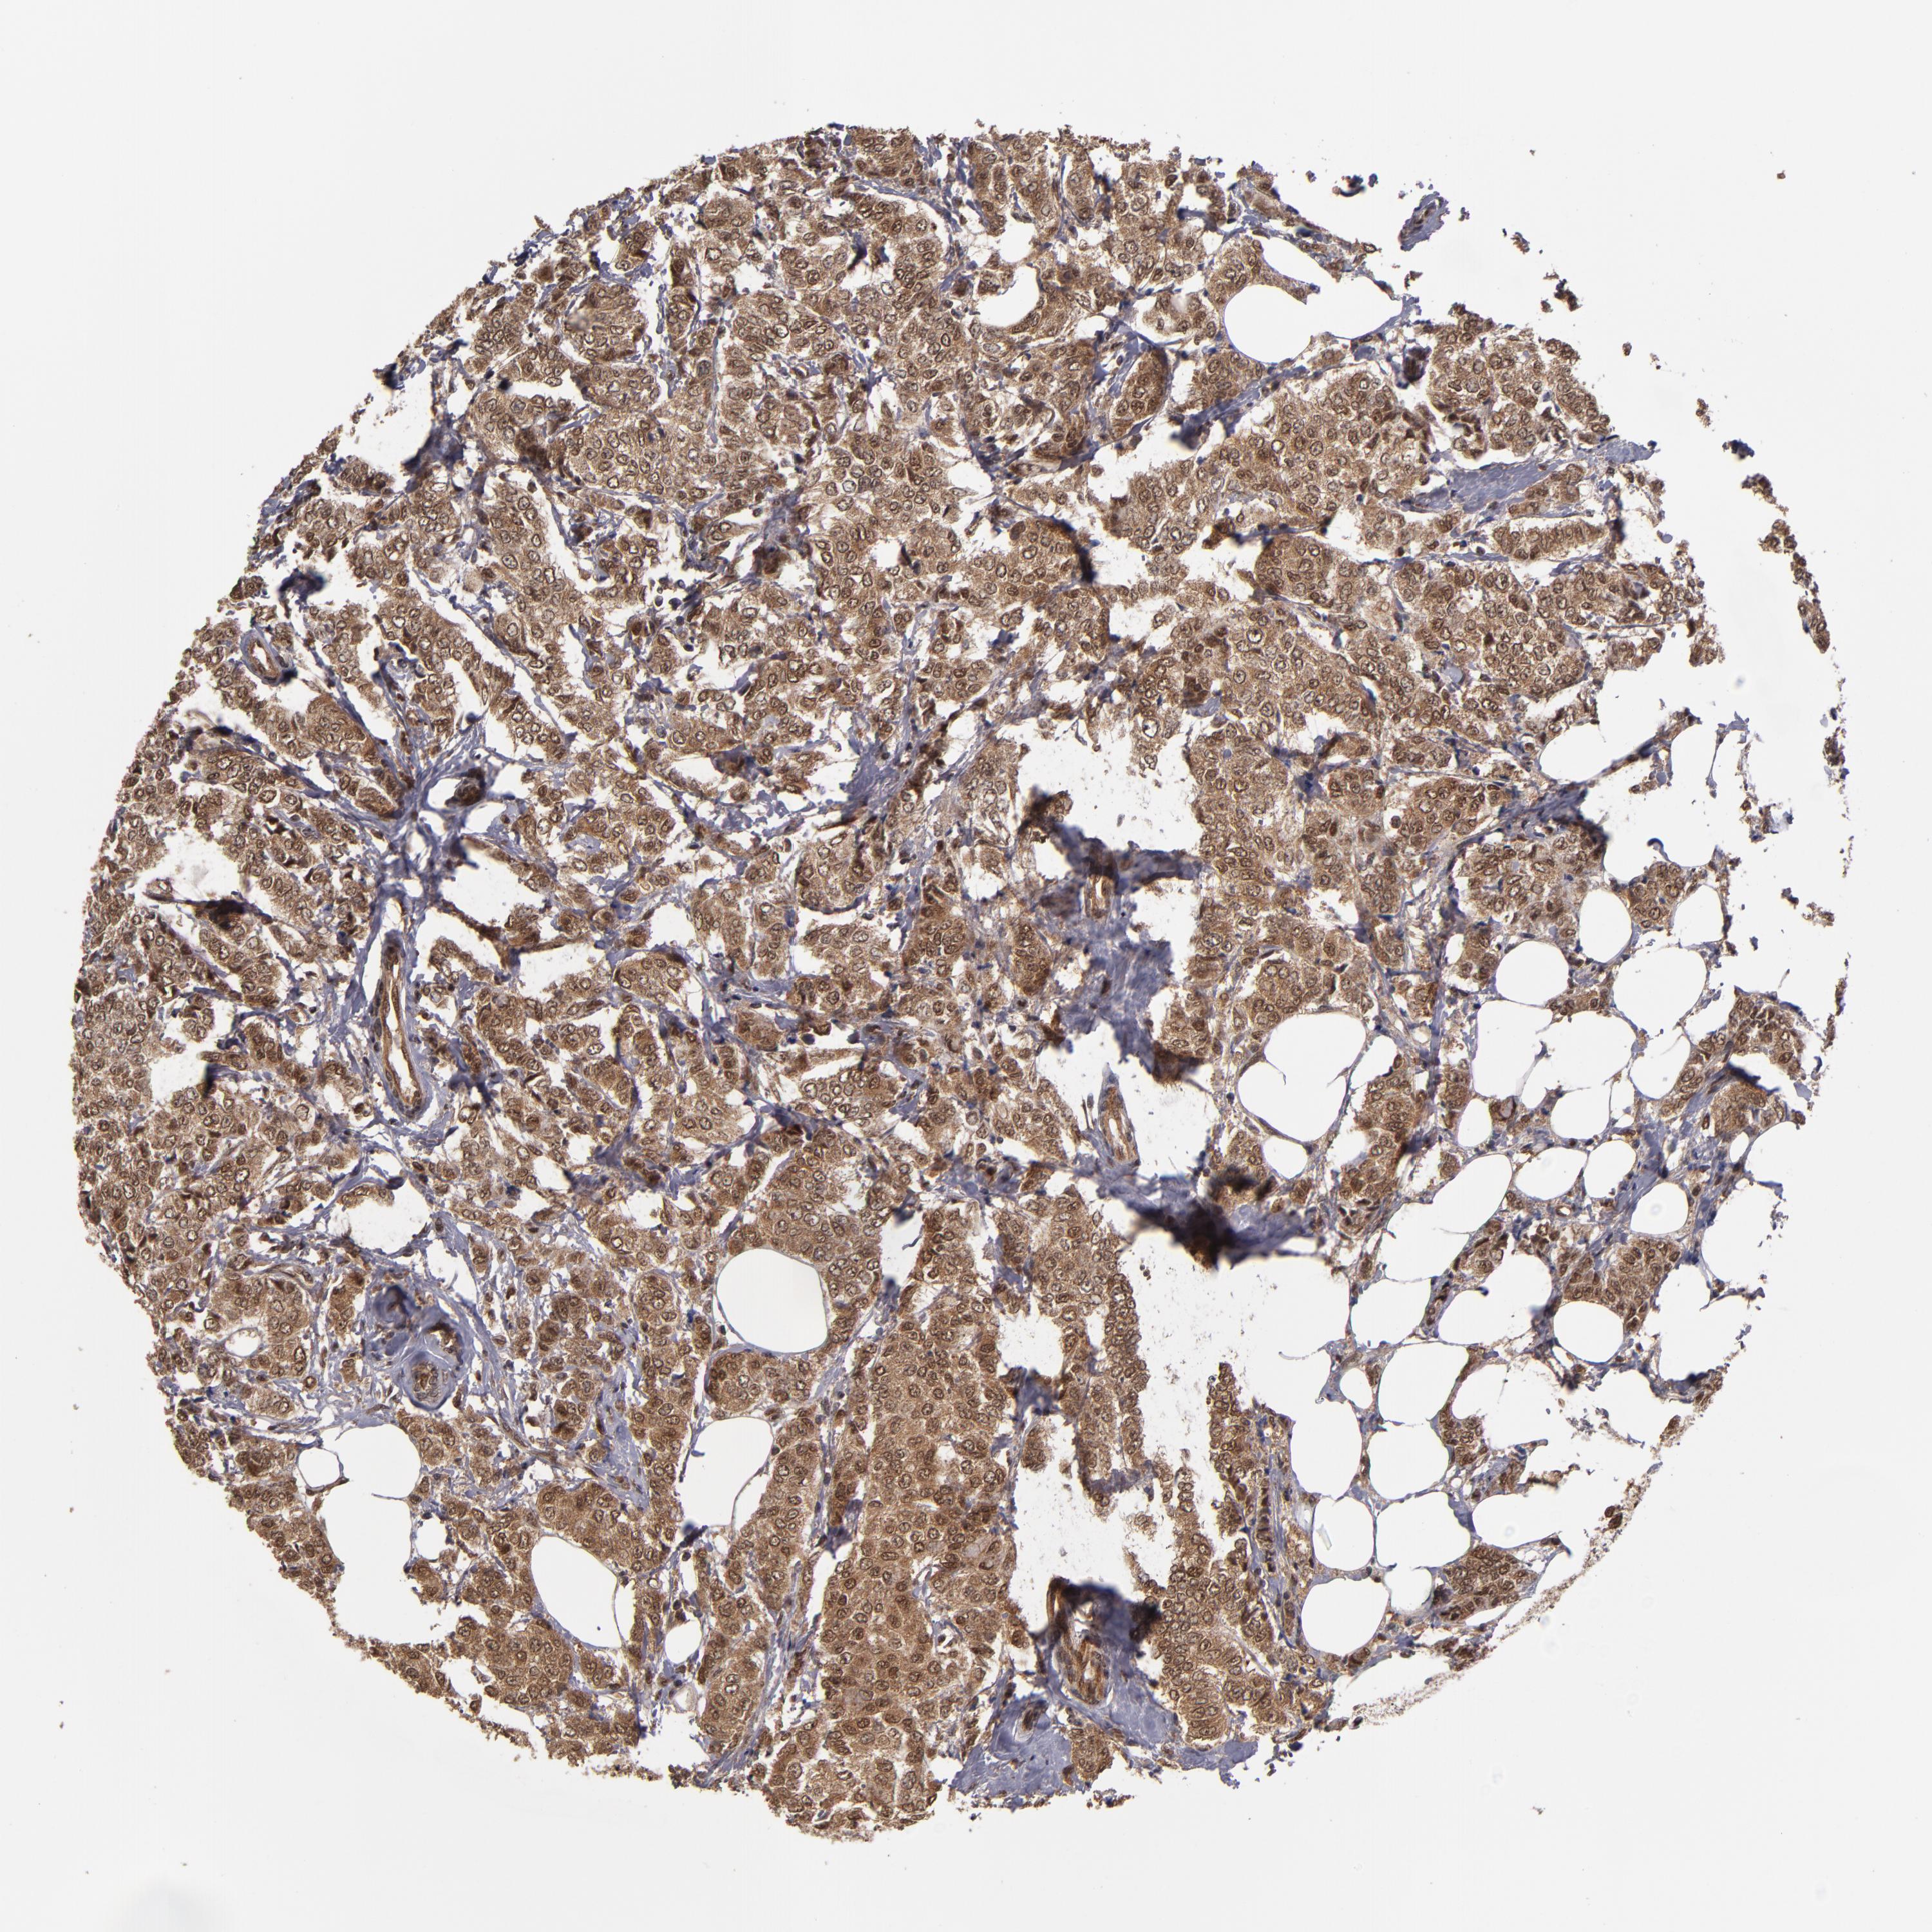

BRCA TCGA BRCA VALIDATION PROTEIN EXPRESSION